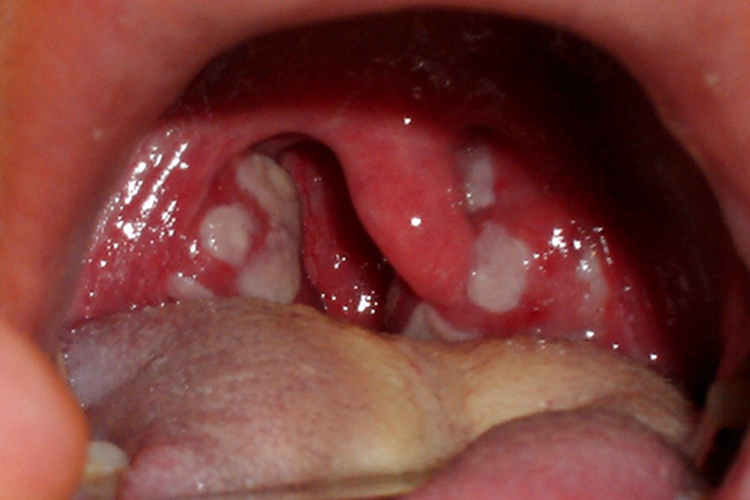

口腔阿弗他溃疡

可以长在扁桃体附近,初起为局限性的黏膜充血水肿,呈粟粒状红点,灼痛明显;继而形成圆形或椭圆形的浅表溃疡,直径5-10mm;数日后溃疡面逐渐生长出肉芽组织并自行愈合,不会留瘢痕。溃疡可单发,也可同时出现3-5个,最多不超过10个,呈散在分布,病情可复发,一般无明显的全身症状。